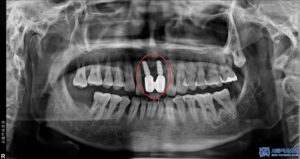

오늘 소개해드릴 환자분도 타 치과에서 받은

상악 앞니 임플란트가 너무

흔들린다며 내원하셨습니다.

임플란트가 흔들린다고 하면

대부분 뼈와 연결된 임플란트 자체에

문제가 있을 가능성을 먼저 의심합니다.

하지만 정밀 검진을 진행한 결과,

임플란트 고정체(뼈 속에 식립된 부분) 자체는

튼튼하게 자리 잡고 있었고,

문제는 그 위에 연결된 보철물과 지대주였습니다.